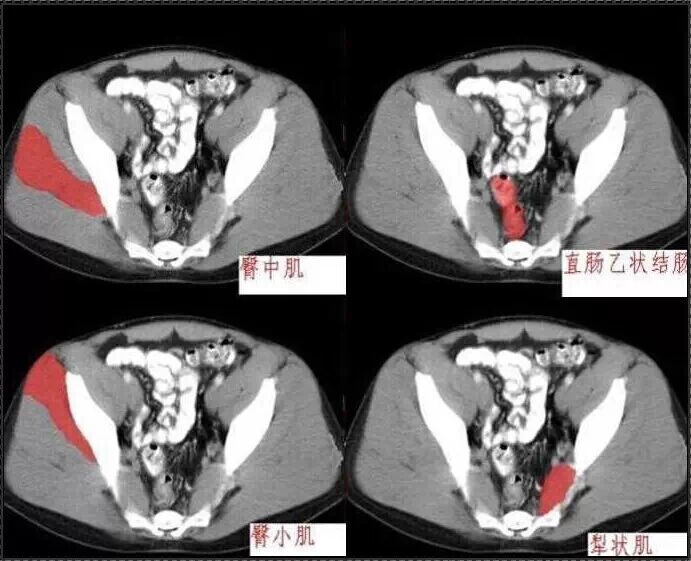

十分钟学会腹部CT解剖(多图)